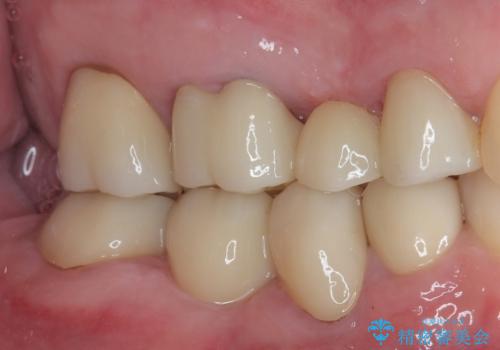

- 左下の4番目のセラミックの詰め物(セラミックインレー)が欠けたとのことで来院された患者様です。以前にセラミックの詰め物の治療を行い、噛み合わせが強く割れてしまっていました。今回はセラミックの詰め物のやり替えだとまた欠けてしまう可能性があるのでフルジルコニアクラウンでの治療を行うことにしました。拡大鏡視野下でセラミックの詰め物、虫歯を除去しフルジルコニアクラウンに適した形に整えました。

歯と歯茎の間に圧排糸と呼ばれる糸を入れてシリコーン印象を行いました。

見た目、機能面ともに満足していただけました。

噛み合わせが強い方なので今後はセラミックが割れないようにナイトガードを使っていただきながら、定期的にクリーニングで通ってもらう予定です。